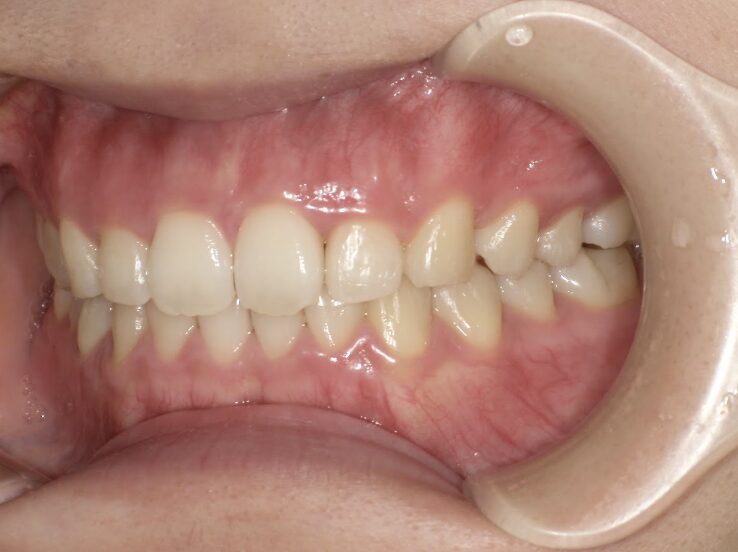

前歯のすき間が気になるを主訴に当院を受診され、前歯部空隙歯列(歯と歯の間に隙間が空いている状態)・過蓋咬合(上の歯が下の歯を深く覆いかぶさっている状態)・下顎前歯叢生(ガタガタ)を認めました。

IPRを使用してマウスピース型矯正装置(インビザライン)を使用し過蓋咬合及び叢生の改善を行いました。